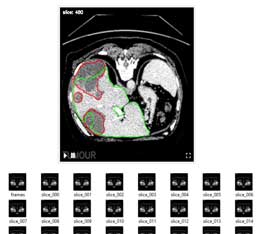

Liver tumour

(CT scan)

- Automatic tumour detection

- Highlight tumour location

- Show tumour existence